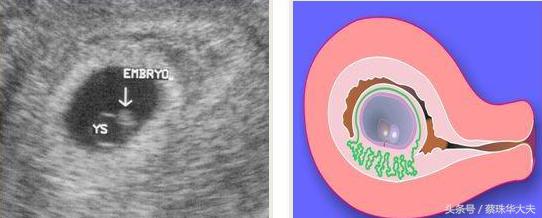

阴道超声准确率比腹部超声高,可以更早的鉴别怀孕是正常还是异常,是宫内怀孕还是宫外孕。

阴道B超探头放在阴道内,只要经过宫颈策划就直接看到在宫腔内的胚胎,哪怕只有很微弱的胎心或是很小的胚芽,都逃不过火眼金睛的小神探 阴道探头。

如果小胚胎长错了位置,长到输卵管内,那小神探也不怕,神探位置稍微变动一下,转到侧穹窿,一会儿就找到卵巢和旁边的输卵管。